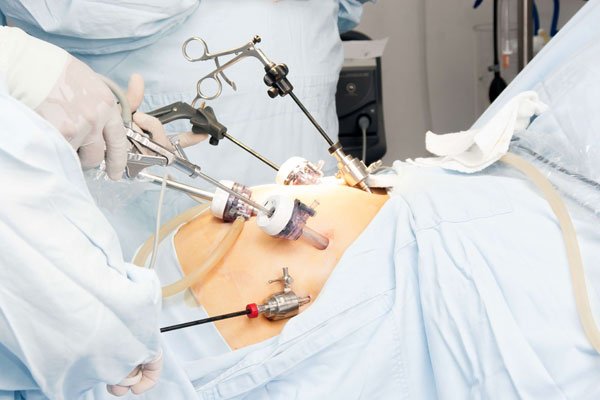

The aim of the General Surgery Department is to provide and implement a...